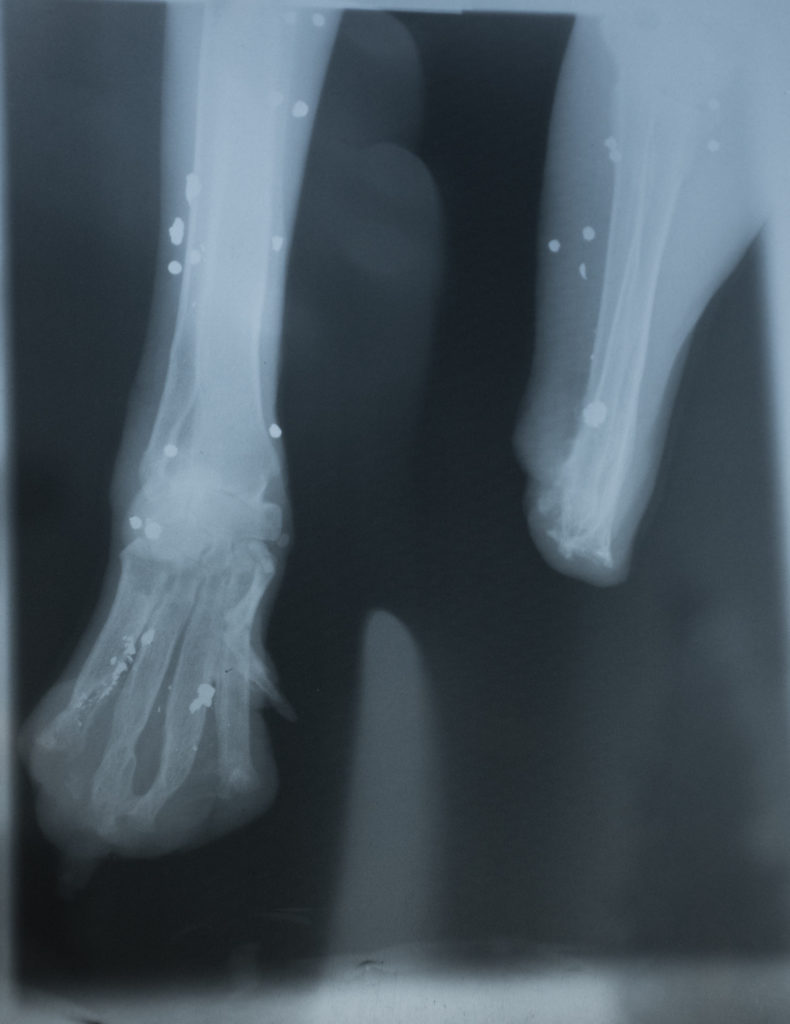

Das wird sehr aufwändig und leider auch teuer. So soll z.B. die Prothese bei einem Anbieter um die 900 € kosten und die Orthese runde 700 €. Das ist wieder ein Batzen Geld. Aber wir wollen doch alle, dass Happy endlich glücklich sein darf, nachdem, was die Menschen ihr angetan haben. Auf den Röntgenbildern kann man sehr gut erkennen, dass sie viele Schrotkugeln oder Teile davon in den Vorderläufen hat. Trotzdem ist sie lieb und geduldig, sehr freundlich, auch zu den anderen Tieren und liebt Streicheleinheiten. Jetzt sind ihre “Pflegeeltern” in eine ebenerdige Wohnung mit Garten umgezogen und für ihr Glück fehlen nur noch die Gehhilfen. Ohne geht es bei ihr einfach nicht.

Wir haben Happys Vorderläufe und zusätzlich ihre Hüften und den unteren Rücken röntgen lassen. Die Vorderläufe wurden gewaltsam abgetrennt, wir wissen nicht, was ihr widerfahren ist. Zusätzlich erkennt man dort viele Schrotkugelfragmente. Die Hüfte ist voll beweglich, nicht deformiert und gut bemuskelt. Nun ist unsere Idee, für sie einen Rollwagen anzupassen, der sie vorne unterstützt, da sie auf dem Stumpf und dem verkrüppelten Fuß nicht laufen kann. Die Hüften dürften kräftig genug sein, so dass sie sich nach einiger Lernzeit damit dann viel besser und müheloser bewegen kann.